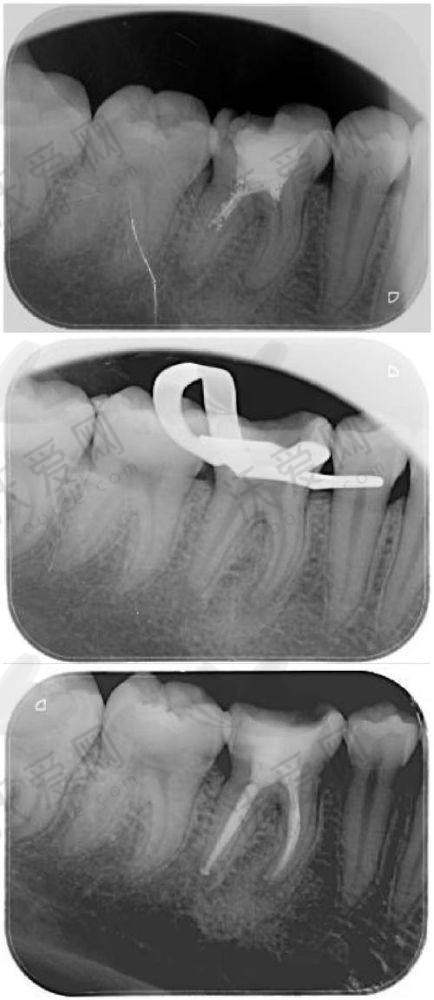

长春传阳口腔在根管治疗方面拥有精良的技术。医生们采用精细的操作手法,能够正确地清理根管内的感染物质。在治疗过程中,运用精良的根管测量设备,严谨测量根管的长度,确保治疗的正确性。同时,采用效率高的消毒技术,对根管进行完全消毒,防止再次感染。而且,医院还引进了精良的填充材料,这些材料具有良好的密封性和生物相容性,能够有效地填充根管,修复牙齿的功能和形态。

根管治疗主要用于治疗牙髓炎、根尖周炎等牙齿疾病。当牙齿的牙髓受到感染时,会引起剧烈的疼痛,根管治疗可以去除感染的牙髓,快速缓解疼痛。对于根尖周炎患者,根管治疗能够清除根尖周围的炎症,促进根尖周组织的愈合。此外,根管治疗还可以保留天然牙齿,避免拔牙带来的不便和后续的镶牙费用。通过根管治疗,患者可以继续使用自己的天然牙齿,保持牙齿的正常咀嚼功能和美观。